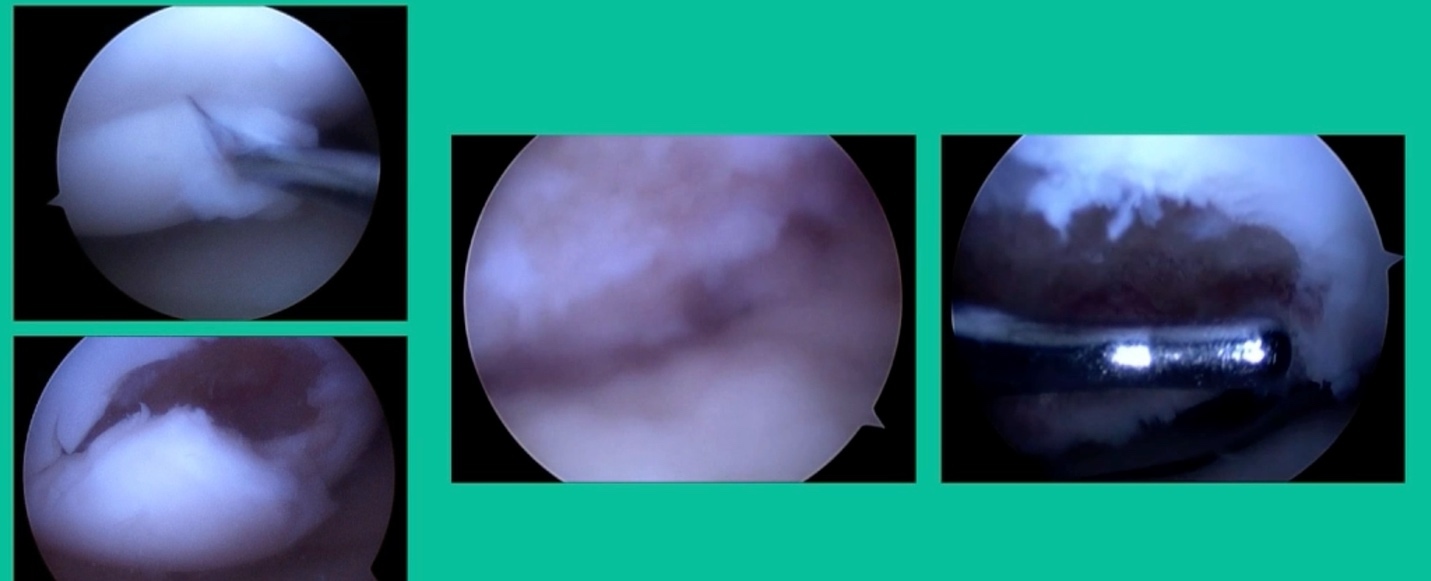

Now a couple of quick cases. This is juvenile OCD. This is the first series of three or four, just juveniles. 14-year-old, intermittent knee pain, lateral femoral condyle OCD (Figure 1).

I thought I might be able to fix it. I had the conversation with the family, get in there, started taking it apart with a Vanguard elevator grasper. Behold, it’s really just cartilage fragments (Figure 2).

There’s two or three of them. We debrided it. It felt normal in six weeks, no complaints in three years. What are the results of juvenile debridement? They’re actually profoundly good. You would never expect this in the scheme of things, but the natural history of removing the piece is actually very good in the juvenile patient. However, once again, fix it if you can. Debride it, if you can’t. If they get symptoms, we restore it, and then never leave unstable fragments.

This is an 11-year-old. Left knee lateral knee pain. Effusions, the same type of classic findings (Figure 3)

You look at this one, you say, “what are you going to see when you get in there?” This is one when you get in there, you say, I’m not even sure I’m in the right knee because you almost don’t see it. That happens in patients who were painful, but they don’t look macroscopically unstable. Pediatric orthopedic surgeons tend to drill these. These are the ones that I see as failures. I think when you’re talking about something that’s mechanically unstable, it’s hard to understand why drilling would actually make it work without fixation. Even if it’s microscopically unstable.